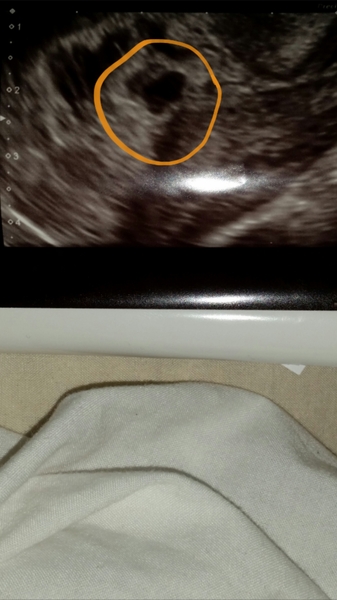

sjd114 · 19/08/2015 11:20

Well basically. . On the paperwork they've given me.. It says..

From Monday -

Gestational Sac - uncertain

Yolk sac - absent

Gestational sac size : 4mm X 8mm X 6mm.

In the notes it said "likely misscarriage"

Today it says:

Gestational sac : present

Yolk sac : present

Gestational sac size :10mm X 8mm X 8mm

To be honest, my brain is broken from it all. I just want a yes or a no, which I know they can't give me just yet. :(

sjd114 · 19/08/2015 11:25

This is what they gave me..